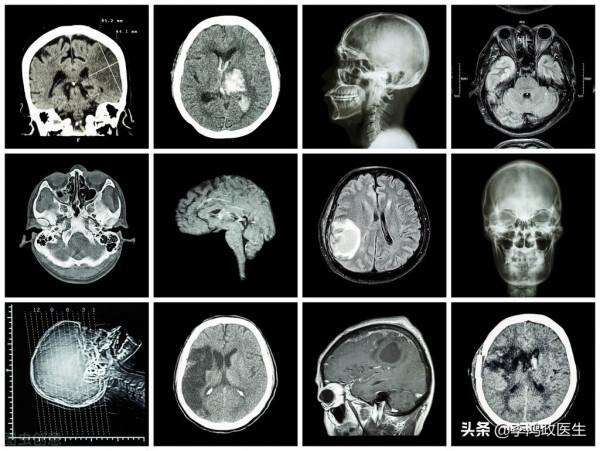

醫生說,不排除有腦出血、腦梗死或者腦炎、腦腫瘤等等情況,最好是做個顱腦CT看清楚一些,無緣無故昏迷那是肯定有問題的。

沒過多久,結果就到了醫生手裡,醫生告訴高小姐,腦袋(左側顳葉)長了個東西。

這個顱腦CT平掃看的不是太清晰,放射科醫生做不了診斷,需要住院,進一步做頭顱MRI檢查,看仔細一些。醫生解釋說。

這回看的更清楚了,影像科醫生和神經內科、神經外科醫生坐在了一起,討論了,認為左側顳葉這個東西是個膠質瘤。

膠質瘤是大腦最常見的惡性腫瘤,但惡性程度也分高低,有些人的很兇險,有些人的比較緩和,得看情況,從目前的影像學來看,可能是個偏惡性的。醫生給出了答覆。